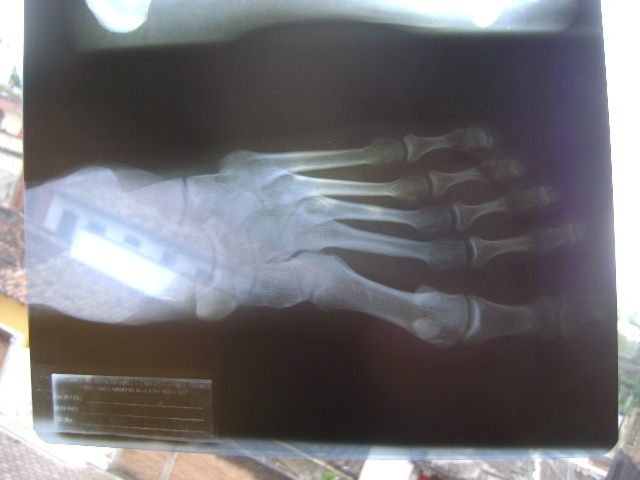

Aquí mis radiografías, nada espectacular en ellas:

Acá se ve el nervio que tengo inflamado, es el nervio dorsal medial, tiene un quiste que se va a quitar si logra desinflamarse con las medicinas que me recetaron y los fomentos de agua caliente con sal una o dos veces al día, tengo consulta de nuevo en 15 días y no puedo correr hasta entonces. Espero que todo salga muy bien, voy a obedecer las indicaciones al pie de la letra para evitar que tengan que infiltrar mi nervio y más cosas en las que ni siquera pensaré por ahora. En el peor de los casos, mi problema sería un neuroma, que es una inflamación de nervio que está apretado por unos zapatos o entre un par de huesos.